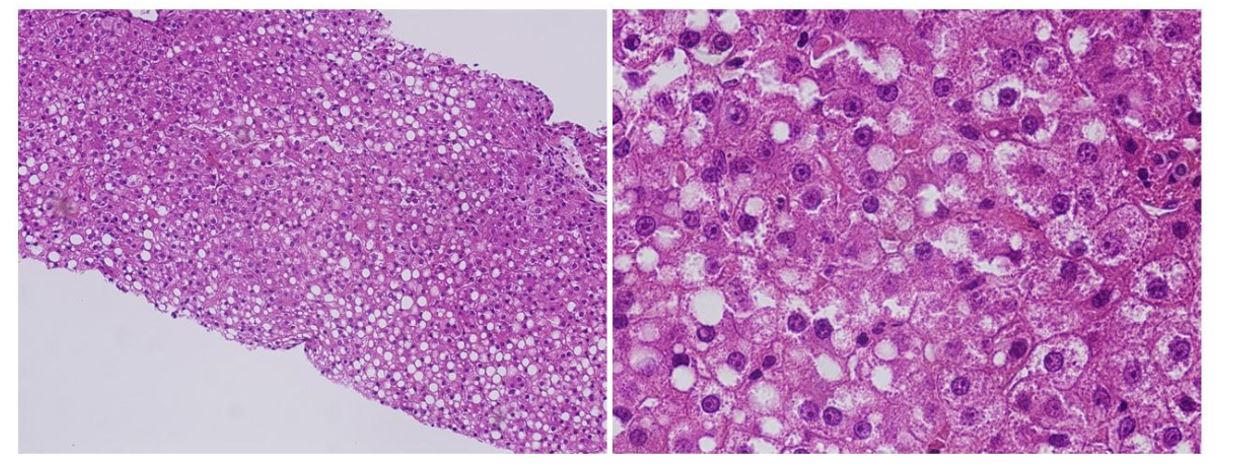

Cerebrospinal fluid (CSF) analysis yielded normal results, including IL-6 and viral culture. However, LAMP (Loop-mediated Isothermal Amplification) for RSV in the CSF was positive for RSV type A. Conventional bacterial culture was negative. Lactic acid and pyruvic acid were normal in the CSF and blood. Analysis of organic acids in the urine showed the increased excretion of adipate, 3-OH-sebacate, and 3-OH-dodecanedioate. He had secondary carnitine deficiency; his free carnitine was 10.92 μM (standard value: 45.6 ± 11.0 μM) and acylcarnitine was 3.93 μM (reference value: 16.2 ± 7.6 μM). Brain MRI displayed a high signal, which was compatible with the encephalopathy observed by diffusion-weighted imaging (DWI) (Figure 1).

Apparent high signal images are shown in diffusion-weighted MRI image. (left: FLAIRimage), (right: diffusion-weighted MRI).

Figure 1: T2 and diffusion-weighted brain MRI

Apparent high signal images are shown in diffusion-weighted MRI image. (left: FLAIR image), (right: diffusion-weighted MRI).